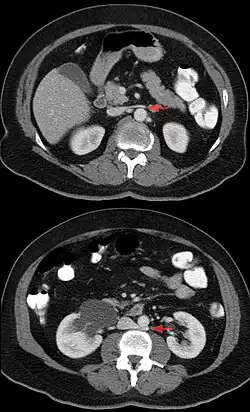

Eine weitere Besonderheit der linken Nierenvene ist, dass sie sich in einer „Gefäß-Zange“ befindet: sie liegt vor der Aorta abdominalis und hinter der Arteria mesenterica superior. Bei arterieller Drucksteigerung kann dies zu einer Kompression der Vene und damit zu einer Abflussstörung der linken Niere (Nussknacker-Syndrom) führen.